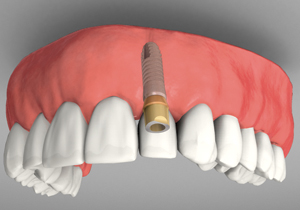

A Missing Front Tooth

An Implant Placed

An Abutment On The Implant

An Implant With A Crown